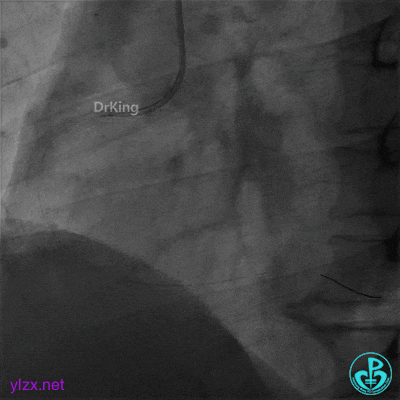

冠脉血栓抽吸导管反复抽吸,未抽出典型血栓。

血栓移位至后三叉,冠脉血栓抽吸导管再次反复抽吸无果,送刺破球囊至RCA病变处再次冠脉内注射重组人TNK组织型纤溶酶原激活剂8mg,等待10分钟后造影示后三叉的血栓完全消失,前向血流TIMI 3级。